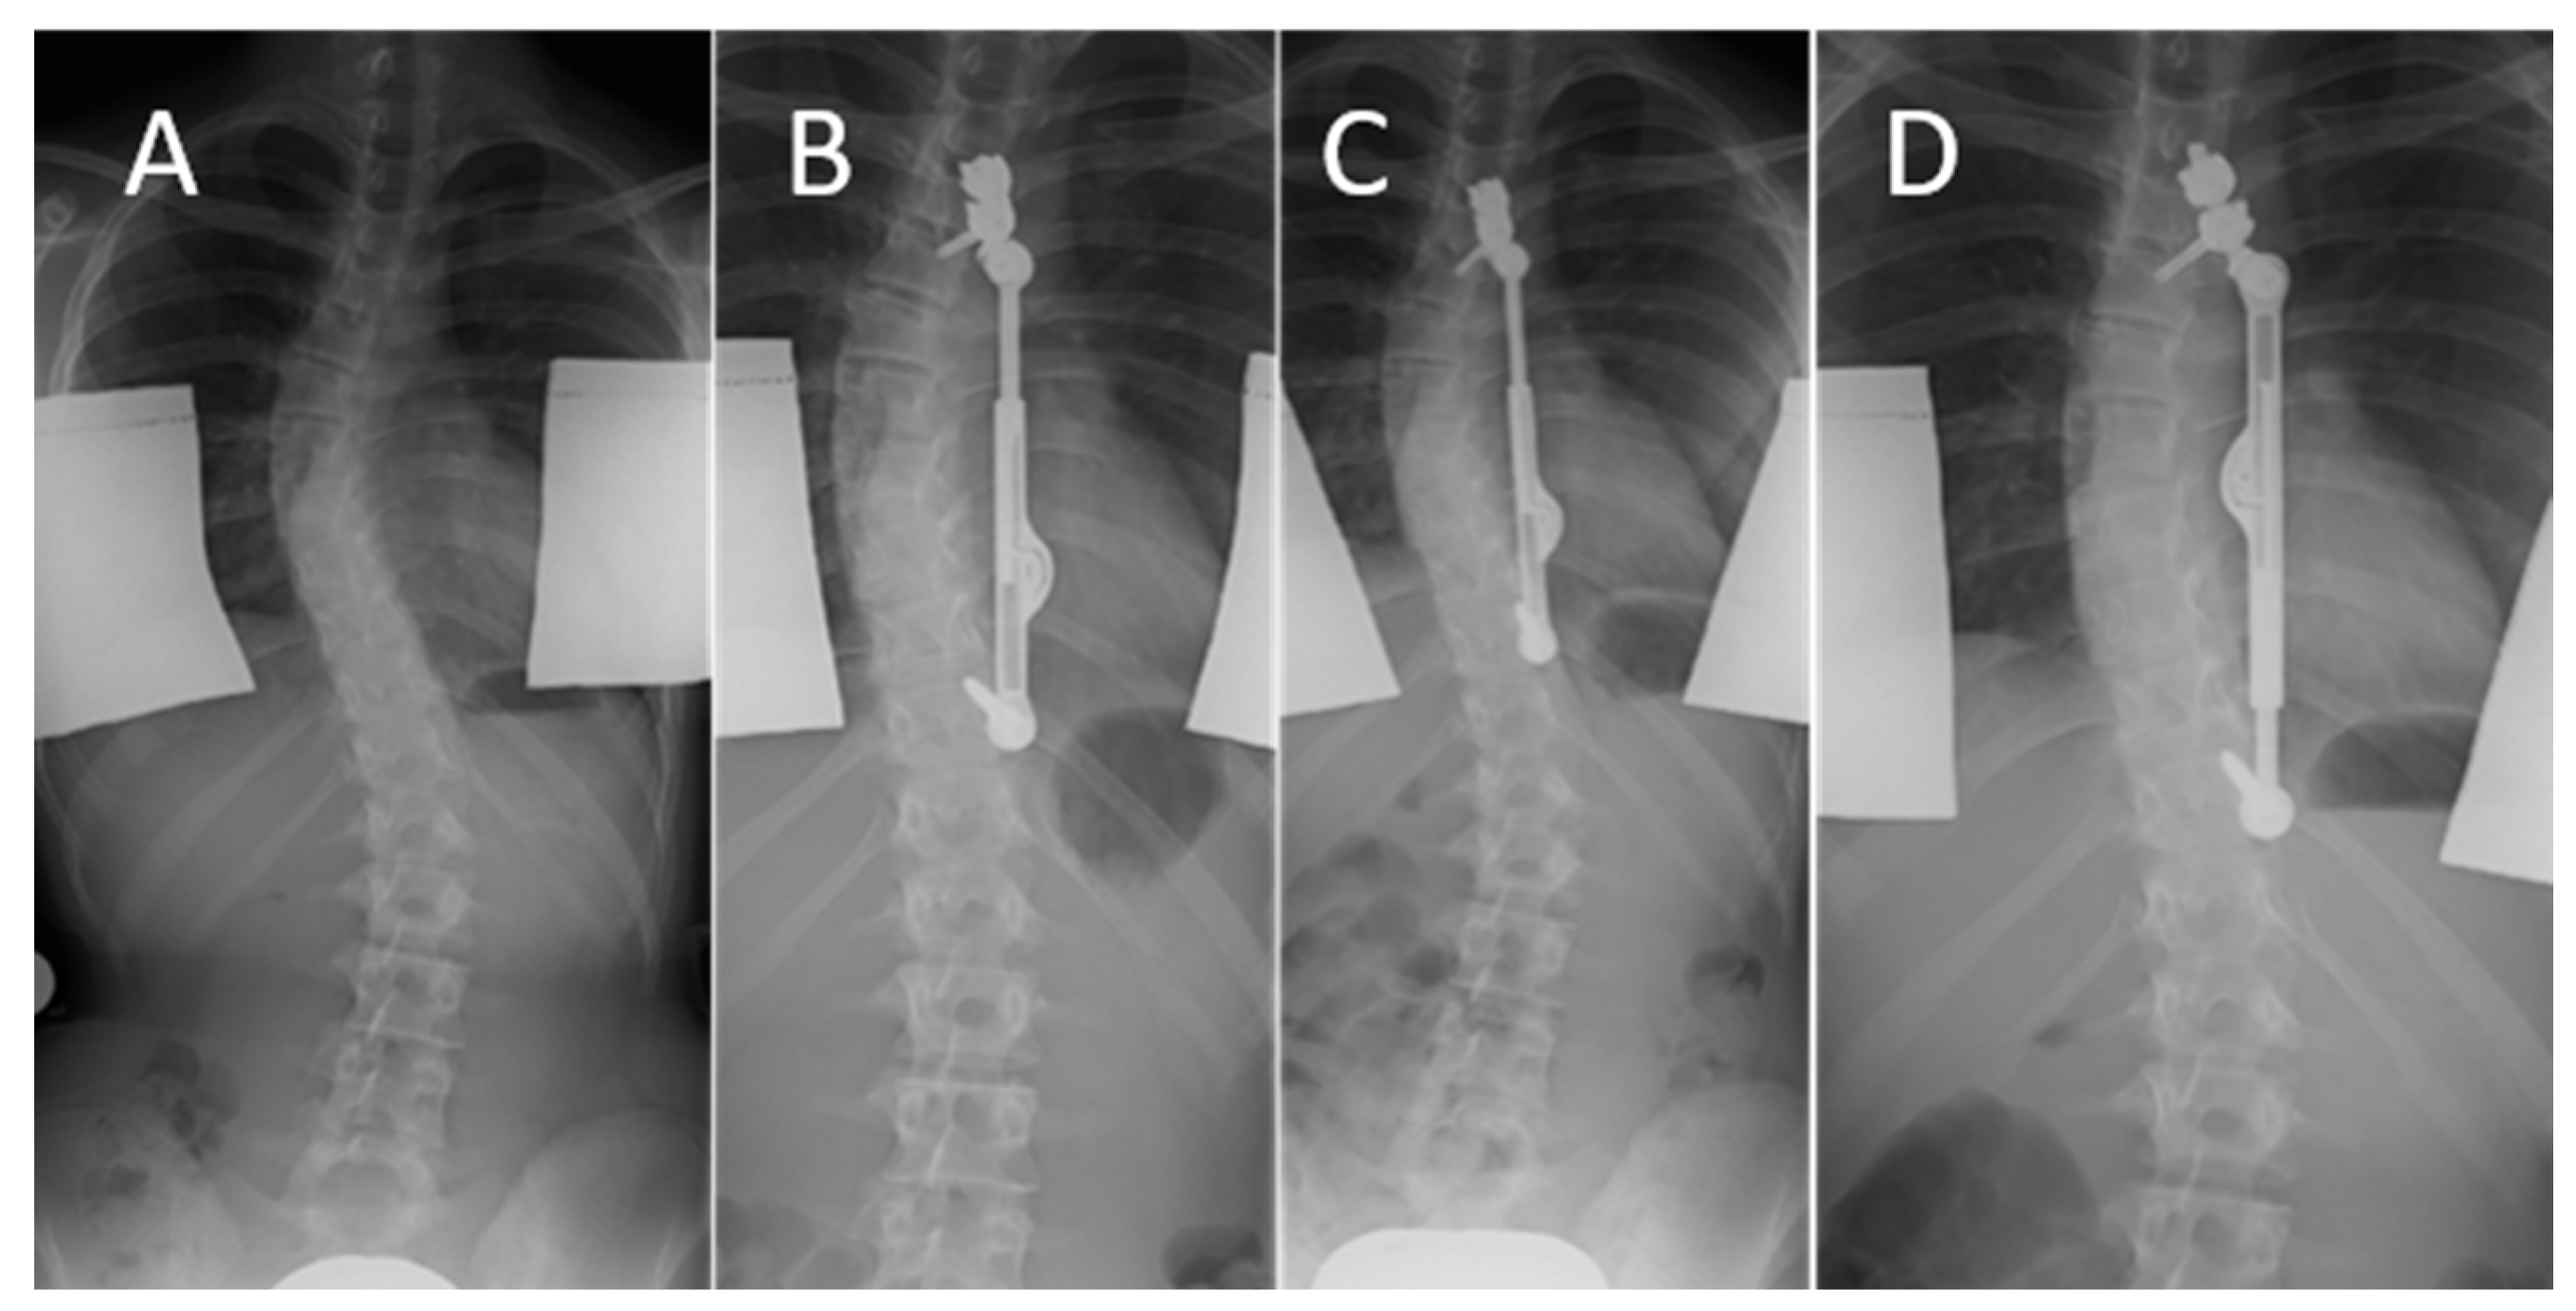

| 13 months | Maximum distraction distance reached after growth spurt, implant replacement with longer implant including renewed intraoperative distraction |

| 18 months | Maximum distraction distance reached after growth spurt, implant replacement with longer implant including renewed intraoperative distraction |

| 20 months | Maximum distraction distance reached after growth spurt, implant replacement with longer implant including renewed intraoperative distraction |

| 22 months | Maximum distraction distance reached after growth spurt, implant replacement with longer implant including renewed intraoperative distraction |

| 19 months | Loss of curve correction | Correction of kite angle, implant replacement with longer implant including renewed intraoperative distraction |